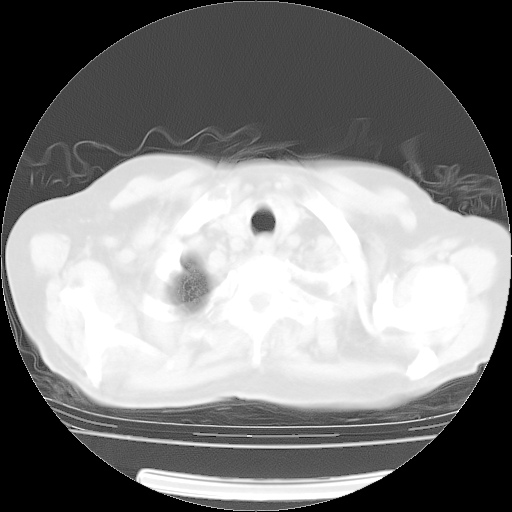

4月28日肺部CT——再次出现类似去年5月9日——透光度降低,(影像科认为)“间质性”改变。

1221483 1 .bmp

1221483 2 .bmp

1221483 3 .bmp

1221483 4 .bmp

1221483 5 .bmp